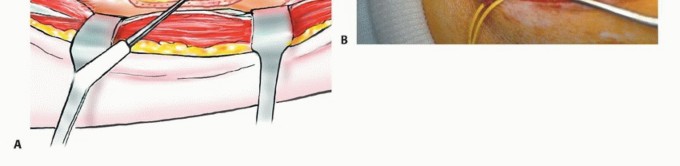

الشق الجراحي (القطع الجراحي)

يُستخدم "الشق الشظوي النفعي" (utilitarian fibular incision)، والذي يسمح بكشف واستئصال الأورام في جميع مستويات الشظية. يمتد هذا الشق من العضلة ذات الرأسين فوق مفصل الركبة، فوق الجزء الأوسط من الشظية، إلى الأمام باتجاه قمة الظنبوب، ثم ينحني خلفيًا وبعيدًا إلى الكاحل. يسمح هذا بتطوير سدائل جلدية عضلية أمامية وخلفية كبيرة.